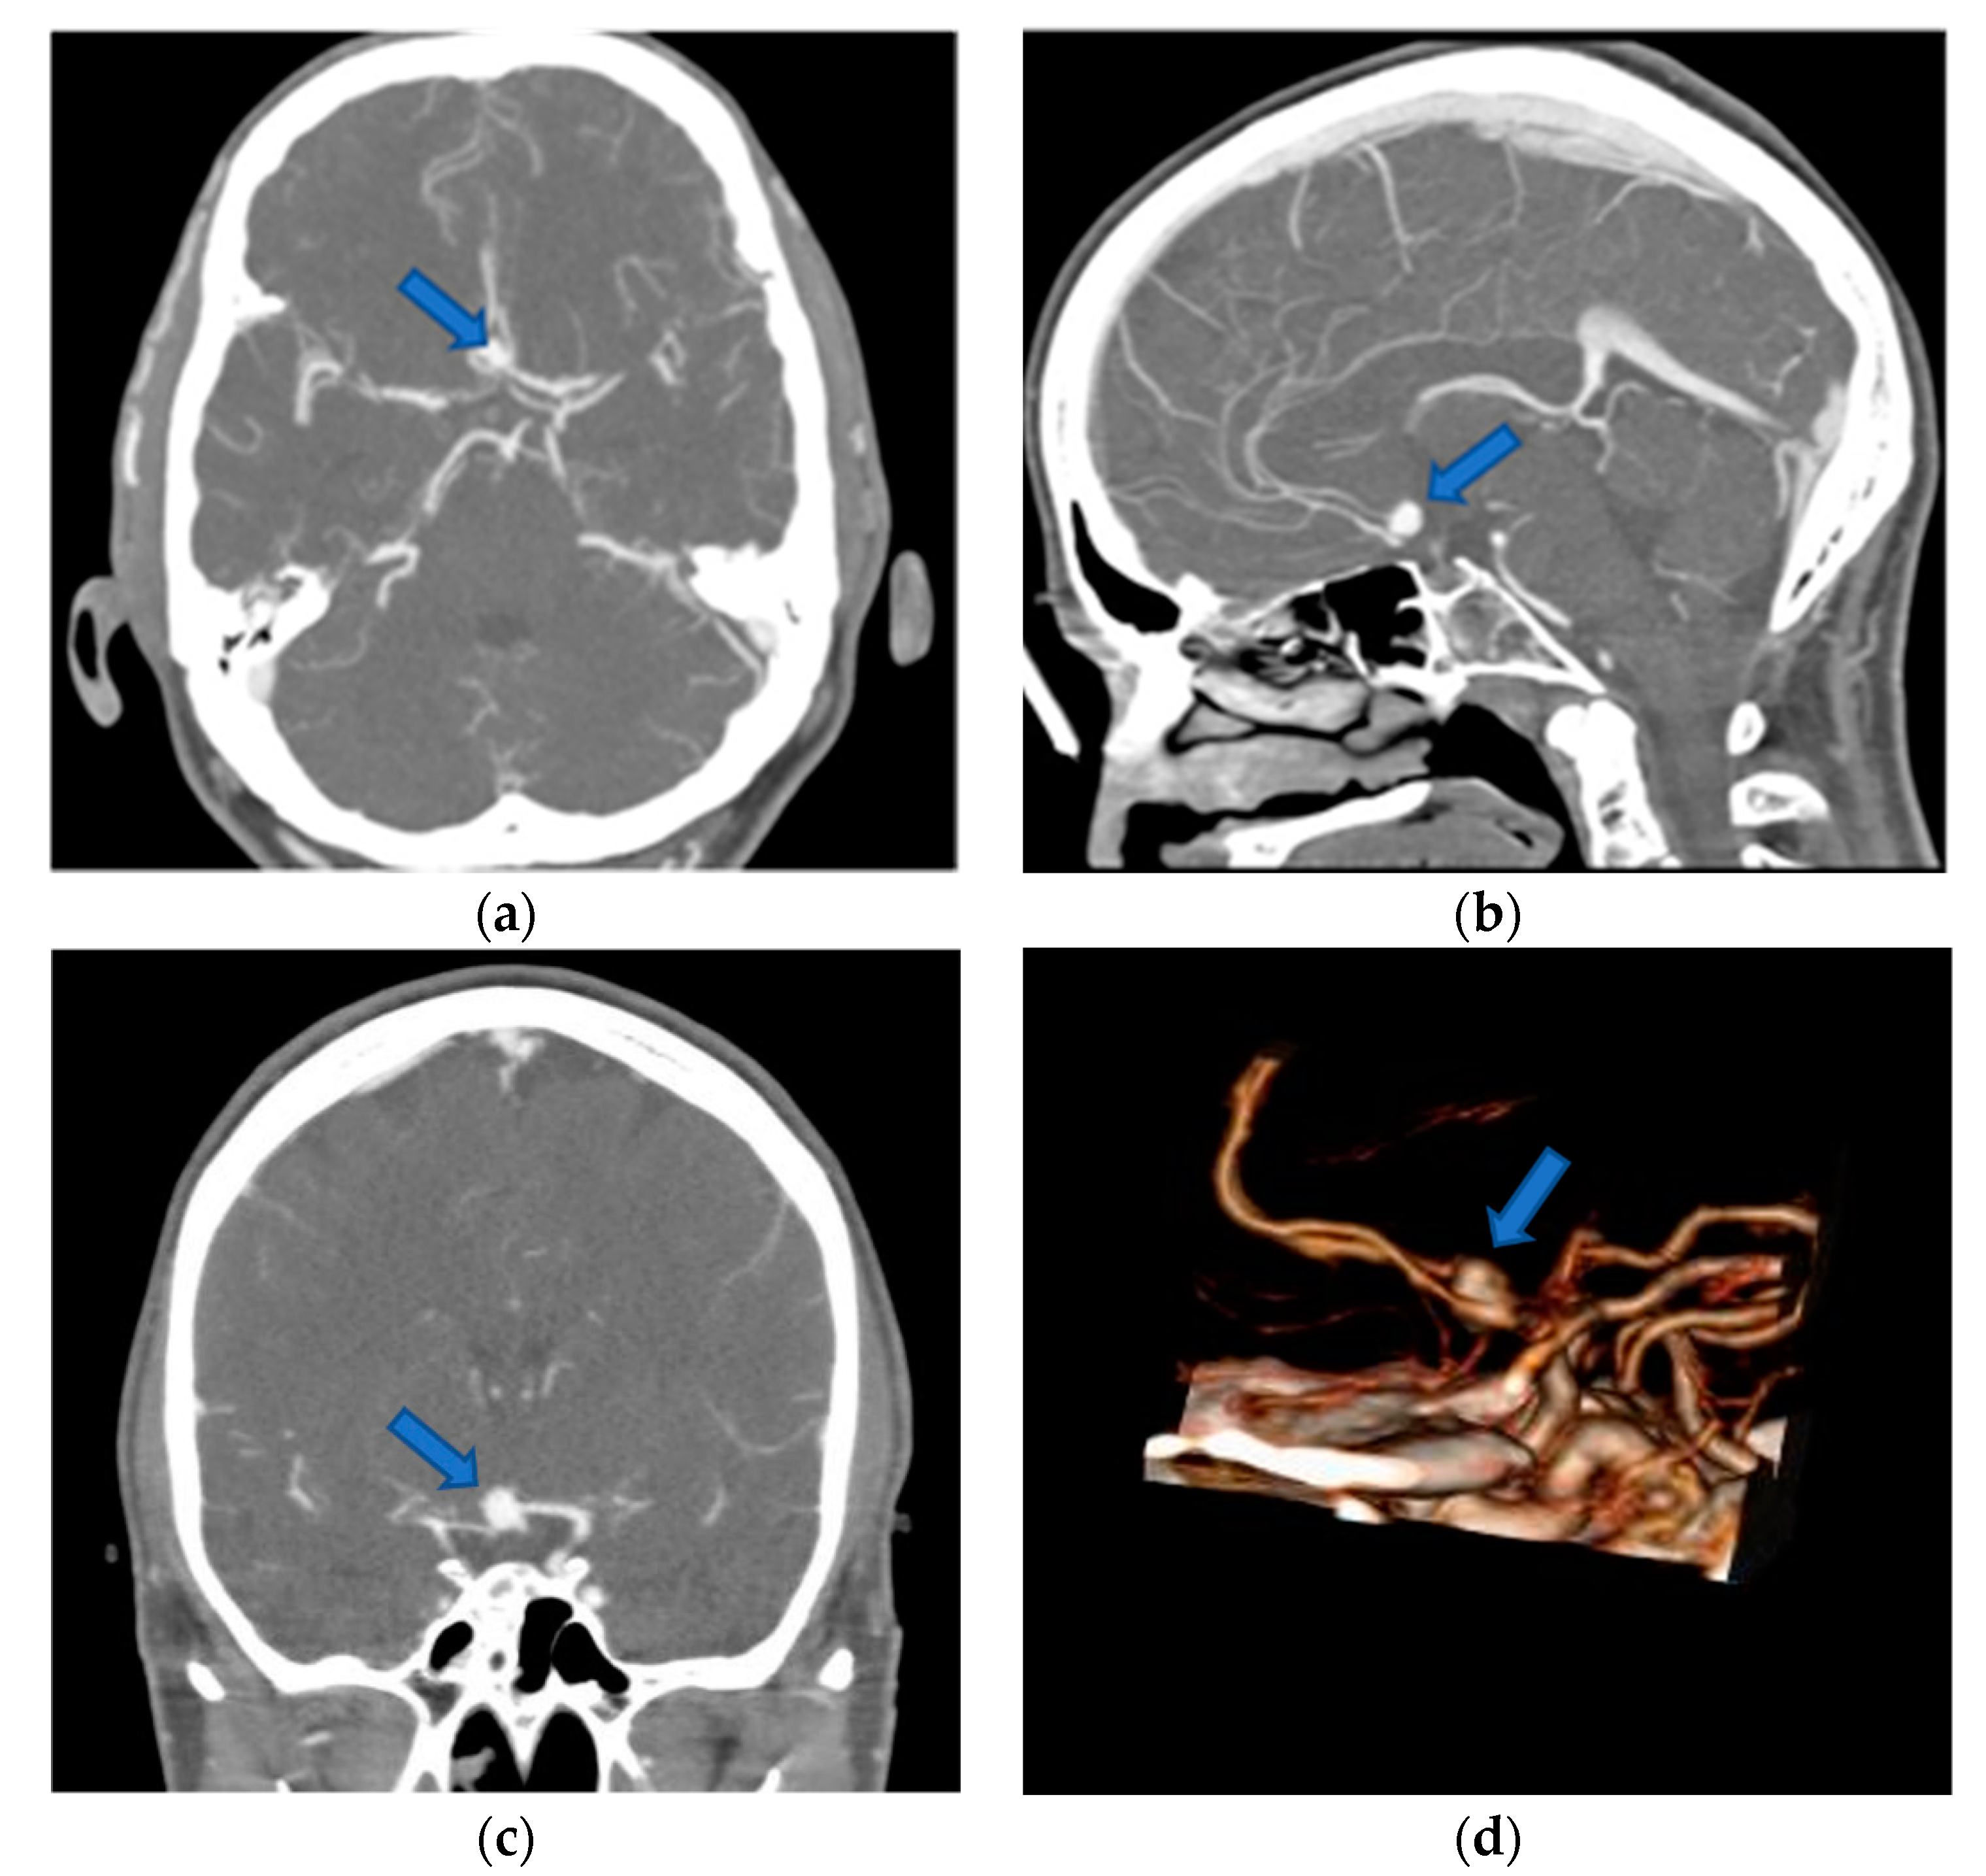

| preoperative imaging: | |

| CTA | 26 (100) |

| DSA | 12 (46) |

| MRA | 20 (77) |